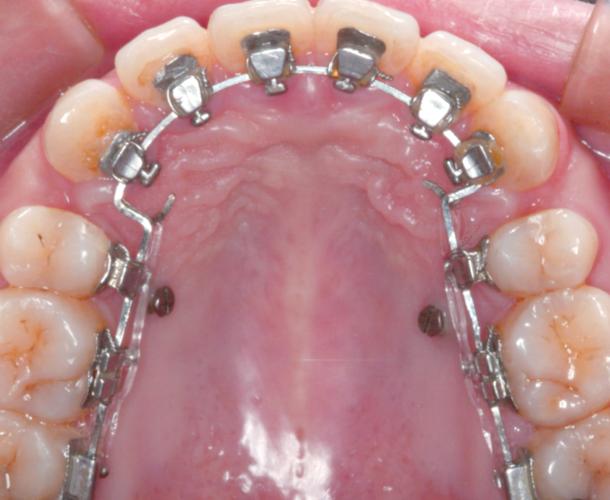

上下颌因骨骼形态、牙弓弧度及咀嚼功能需求不同,托槽的粘接位置存在显著差异,上颌牙弓较大,前牙区牙根较直,托槽通常位于牙齿唇颊面中上1/3处,槽沟与牙长轴平行,以对抗矫正过程中可能出现的牙齿伸长趋势;下颌牙弓较小,后牙区常有补偿性舌倾,托槽位置需偏中下1/3,避免与对颌牙咬合时发生干扰,上颌第一磨牙托槽常设计有圆管(用于放置口外弓或辅弓),位置偏龈方,以增强抗旋转能力;而下颌第一磨牙托槽则更偏中份,优先保证近远中向的稳定性。

受力方向上,上颌托槽需重点控制垂直向力(如压低后牙、纠正深覆合),因此托槽底板与牙面粘接角度常设计为5°-10°的冠向倾斜;下颌托槽则需侧重水平向力(如纠正反合、解除拥挤),托槽底板多与牙面平行或略带龈向倾斜,以抵抗牙齿舌倾趋势,临床中,若上下托槽位置错位(如下颌后牙托槽粘接过高),易导致咬合创伤或矫正效率下降。